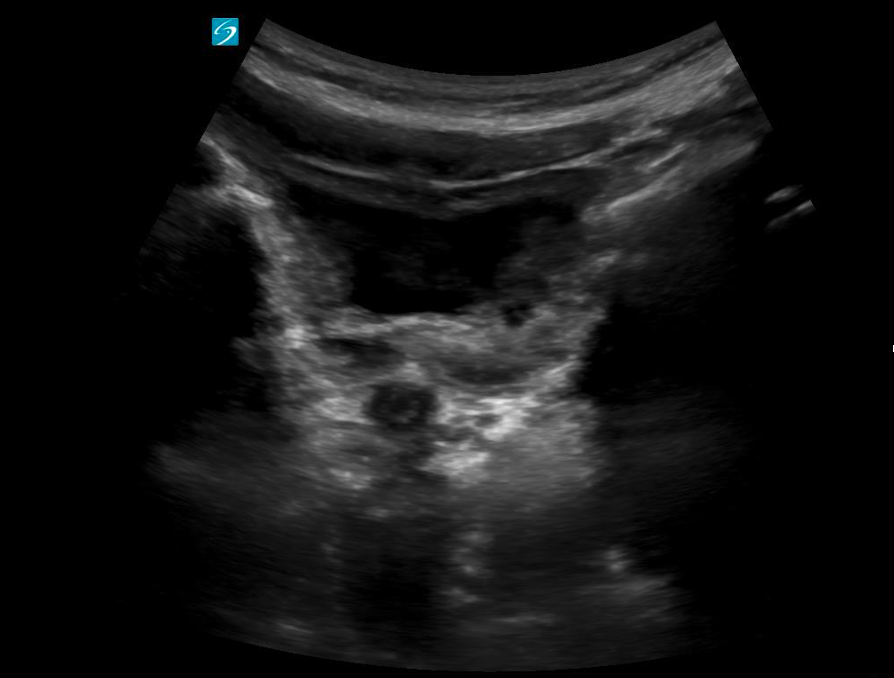

Debris

Debris within the bladder lumen in non-catheterized patients is not considered normal and may indicate an underlying issue. Additionally, dense debris (seen as echogenic masses or clumps within the bladder) in catheterized patients is also not considered normal and may suggest complications such as infection, bladder stone formation, or catheter-related obstruction.

If the bladder remains distended after catheter drainage, it may indicate that the Foley catheter is either obstructed or mispositioned, preventing complete drainage (Figure 15).

Figure 15: Distended bladder despite Foley catheter in situ, suggesting the catheter is clamped or obstructed. Video courtesy of Dr. Dave Kirschner, used with permission.